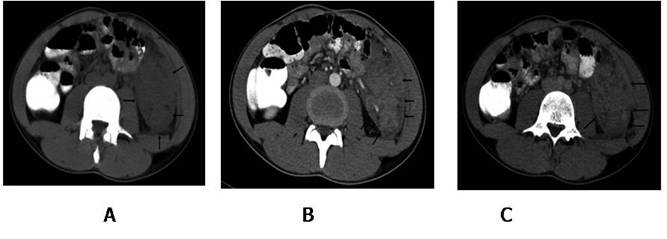

Figure

1: Axial computed tomography image show a soft tissue mass, located between

left psoas muscle and lateral abdominal wall. The lesion partially surrounds

the sigmoid colon (A). Contrast enhanced CT arterial (B) and venous (C) phase

show marked heterogeneous involvement.